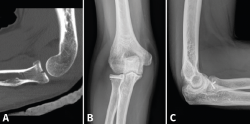

Figura 3. Ejemplo de fractura de Mason II tratada con 2 tornillos de minifragmentos canulados. A: imagen sagital en tomografía axial computarizada (TAC); B y C: radiografía anteroposterior y lateral de control a los 6 meses.

- Reducción abierta y fijación interna (RAFI): el objetivo es obtener una fijación anatómica y estable. Usaremos tornillos canulados de minifragmentos a compresión, sin cabeza, que dejaremos a nivel subcondral (Figura 3). Si existe afectación del cuello, lo ideal es sintetizar primero los fragmentos de la cabeza y añadir después algún tornillo hacia la diáfisis o una placa de bajo perfil (Figura 4)(13).